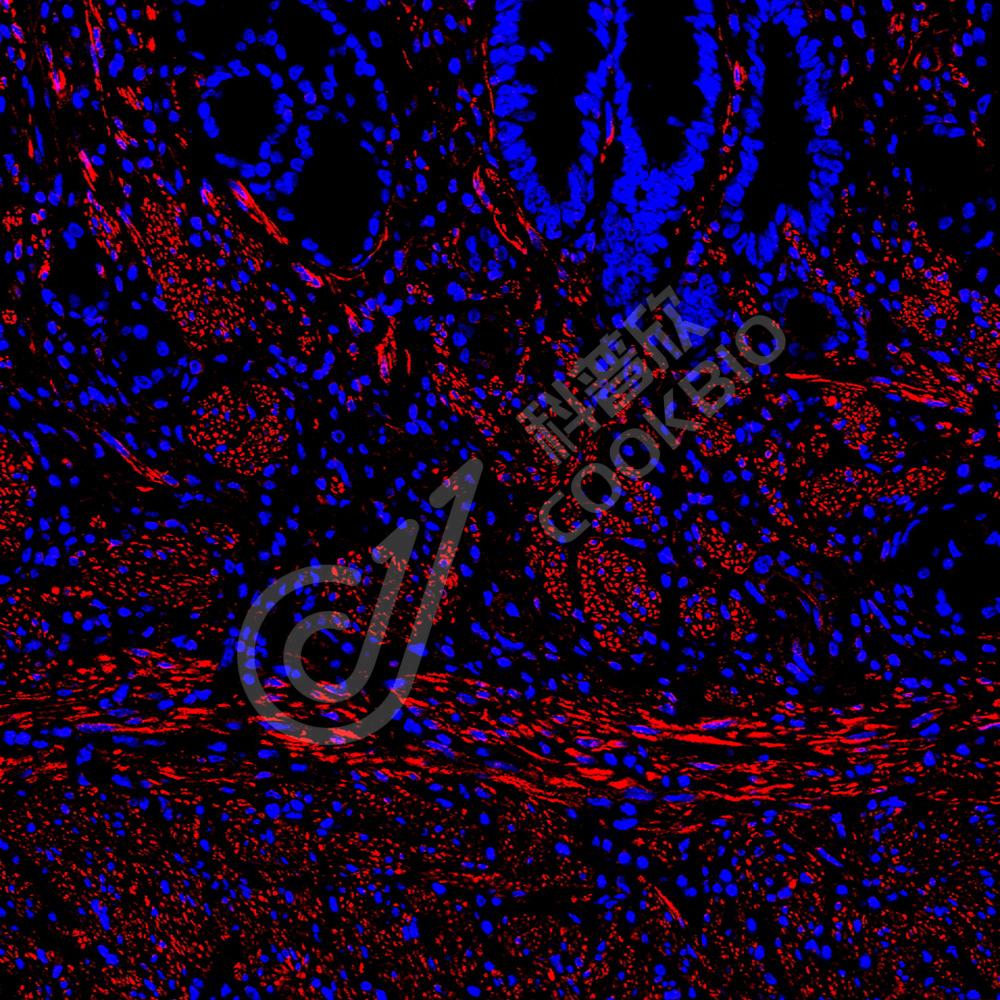

IF检测Desmin蛋白(货号 K236225)(红色).

样品: 小鼠胃, 4%多聚甲醛 (货号KSG1101) 固定12-24小时.

抗原修复: 柠檬酸抗原修复液(干粉, pH 6.0) (KSG1201), 高压锅均匀喷气计时2分钟.

封闭: 3% BSA(货号KSGC305010)的PBS溶液, 室温孵育30分钟.

—抗: 1: 1300稀释, 4℃ 孵育过夜.

二抗: Cy3标记山羊抗小鼠IgG (H+L) (货号KB63903), 1: 300稀释, 室温孵育1小时.